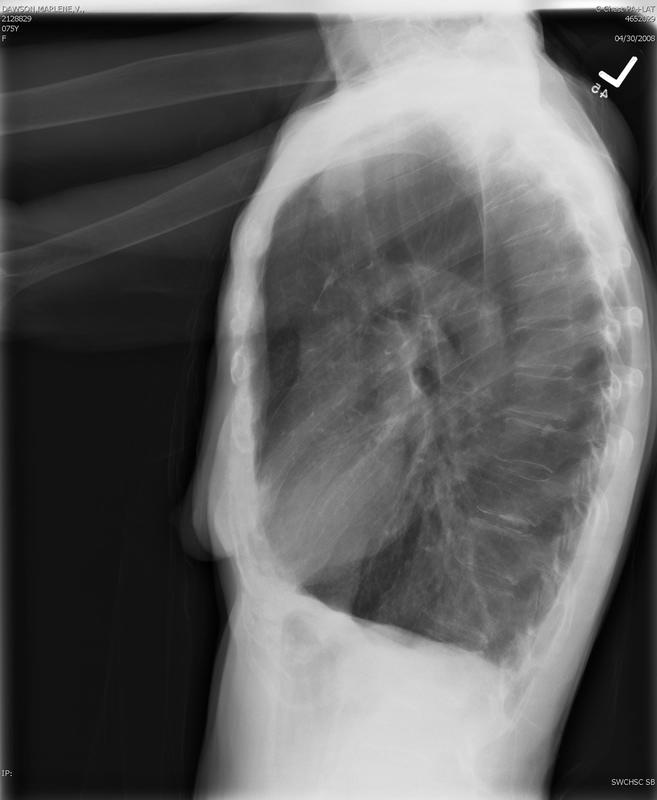

COPD

Emphysema Lat